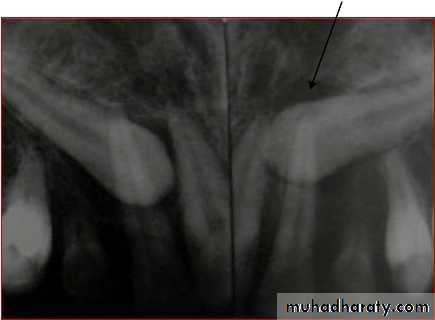

Lateral Cephalogram

Perapical view

First and the most simplest viewAdvantages

1) Root development, pattern and

integrity

2) Crown resorption

3) Root resorption of adjacent tooth

4) Minimum of surrounding tissue is

exposed which increase

accuracy and resolution.

5) Minimal radiation exposure

Disadvantage

1) 2D picture of 3D object

2) cannot determine bucco-lingual

position of tooth & vertical

position of impacted tooth.

Tube shift technique or Clarke

technique (parallax method)

Principle:

• 2 periapical views of the same object are taken from slightlydifferent angles which can provide depth to the flat 2-D

picture depicted by each of the films individually.• Useful in distinguishing the buccal or lingual displacement of

Mesialangulation

Normal

angulation

Distal

Procedure:

1.In the periapical film, the X-rayis taken in the area of interest

with the X-ray beam passing

perpendicular to a tangent to

the line of arch at this point & at

an appropriate angle to

horizontal plane.

2.In the second film, the X-ray

tube is shifted mesially ordistally round the arch but held

at the same angle to the

horizontal plane. The X-ray

tube should describe between

30-450 of an arc of circle whose

Result:

• It is based on the SLOB principle.

• If the object has moved on the same side as thatof the X-ray tube it is lingually placed & if it has

moved on the opposite side it is on the buccalside.

Disadvantage:In cases when canine is highly placed, and

Periapical film shows no superimposition of canine

with the roots of erupted tooth or when

Vertical tube shift method

Left canine is highly placed in OPG. In IOPA left canine moves towards apical 1/3 of lateral

incisor.73